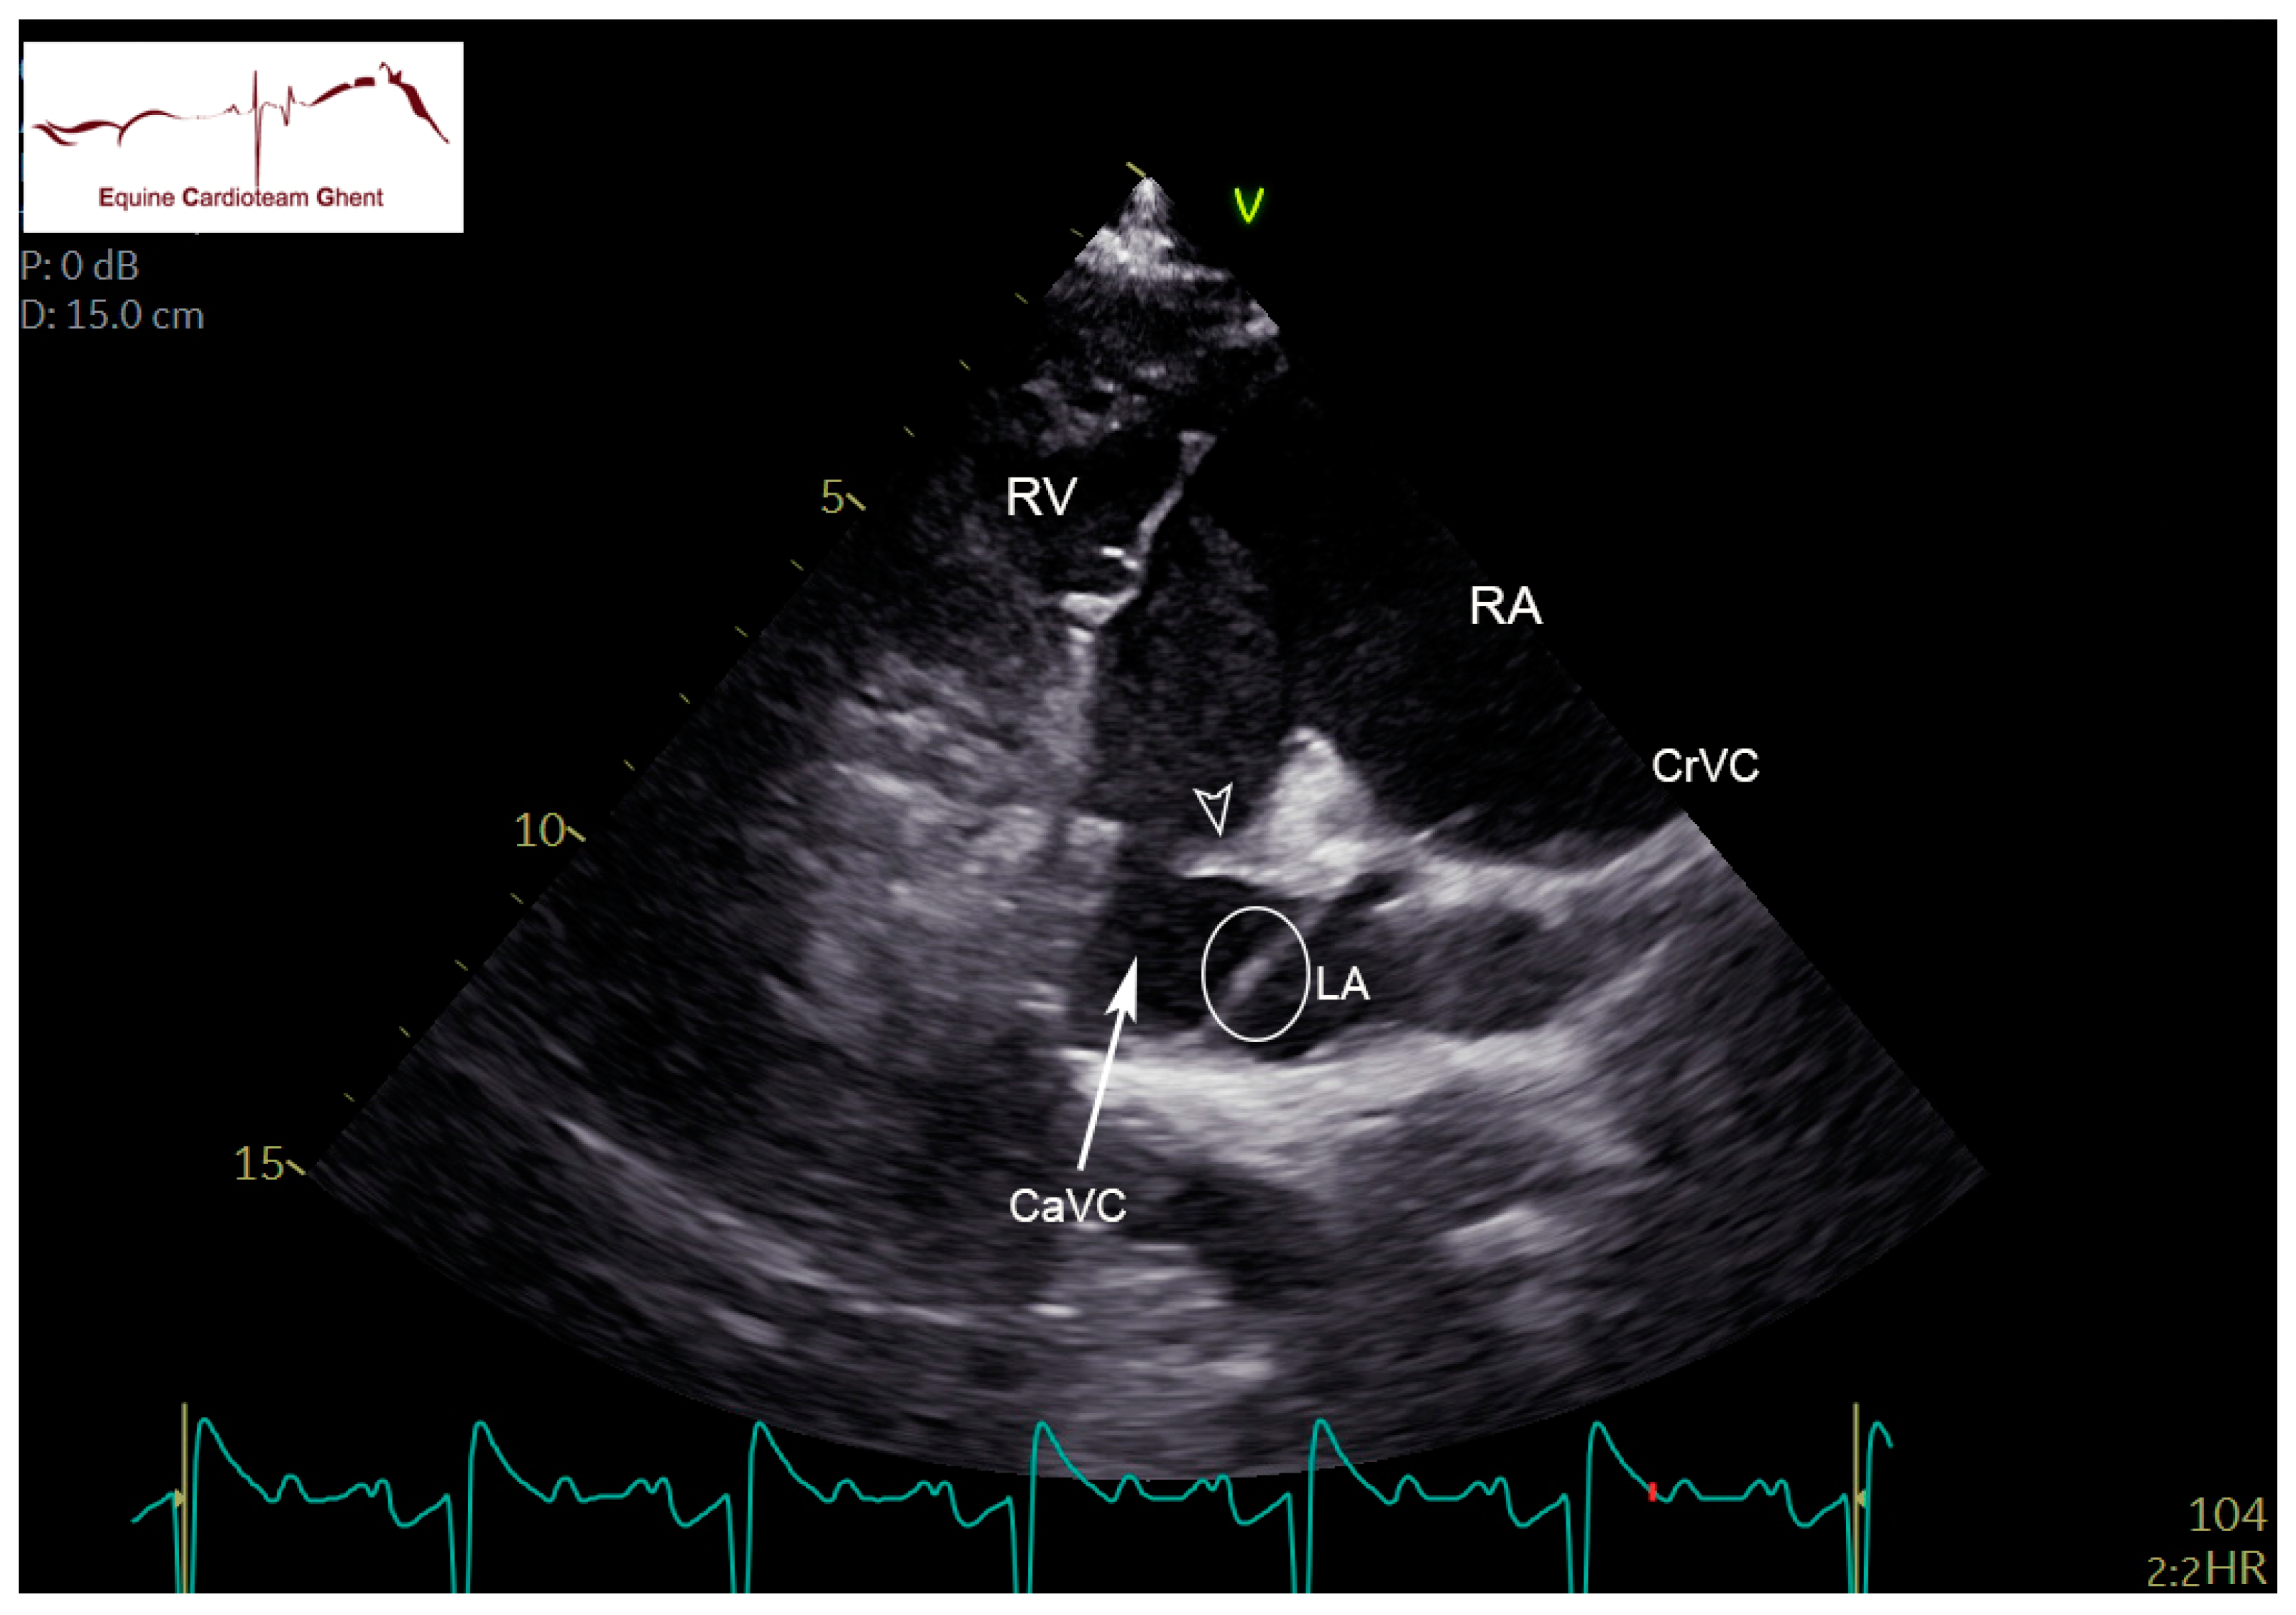

2.2. Echocardiography and Flow Doppler Examination

4. Discussion